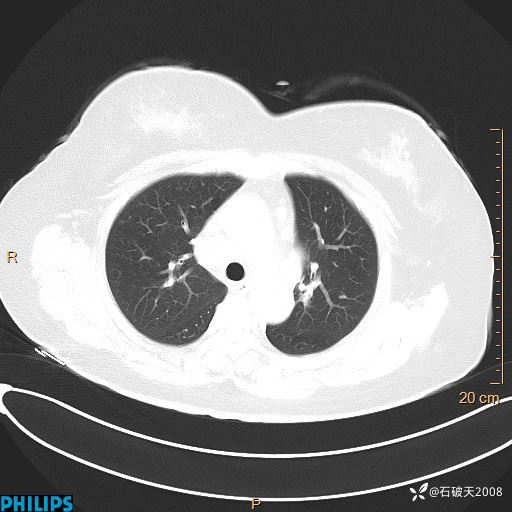

肺结节病?纵膈型肺癌?淋巴瘤?有点意思,欢迎围观

女 52岁 主 诉:咳嗽10余天,咳痰2天。

现病史:10余天前无明显诱因出现咳嗽,呈阵发性干咳,伴咽喉部发痒,无咽痛,无咳痰,无鼻塞、流涕、打喷嚏,无发热、畏寒、寒颤,无头痛、头晕,无胸闷、胸痛,无反酸、烧心,无腹痛、腹泻,无尿频、尿急,无皮疹等,在当地诊所求治,给予口服药物治疗(具体不详),病情无好转。遂在当地社区卫生服务中心开具口服药物治疗(具体不详),疗效欠佳。2天前出现咳痰,在我院门诊求治,行胸部CT提示肺部感染,建议住院,患者要求口服药物治疗,目前仍咳嗽、咳白色粘痰,白天量多,夜间自觉喉部喘鸣音,遂再次来院就诊,以“肺部感染”为诊断收入院。发病以来,神志清,精神可,饮食可,夜间睡眠差,大小便正常,近期体重无明显变化。

动脉期

静脉期